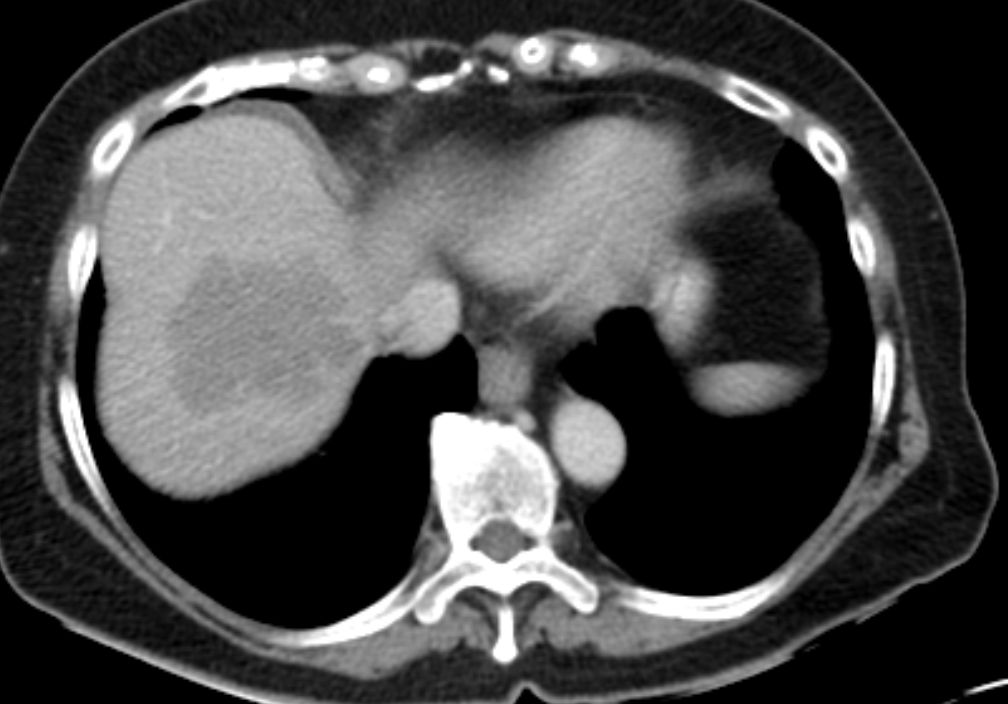

76-jährige Frau, die vor 13 Jahren ein Ovarial-Karzinom pT3b pNo Mo Lo Vo G2 hatte. Radikale OP, 6x Taxol - Carboplatin. Jetzt Lebermetastasen, RF linker Adnexbereich.